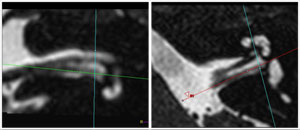

MRI imaging of the inner ear